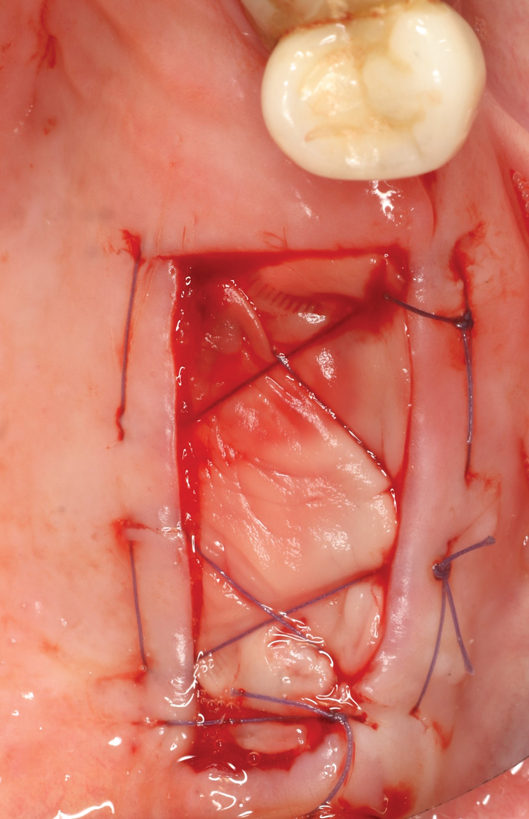

Fig 13. Flap closure and suturing after graft and membrane placement at maxillary left quadrant.

Figure 13